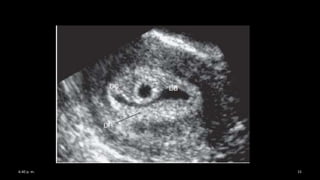

• Signo de la doble burbuja (saco vitelino y amnios)

• Vía transvaginal a las 6 semanas con embrión de 2 mm

• Vía transabdominal entre las 7/8 semanas

• El embrión se sitúa entre ambos

• En caso de no estar puede ser pasajero por

crecimiento lento

• Y de no aparecer se trata de un embarazo

anembrionico por reabsorción del mismo

• Se fusiona con el corion entre las 11-13 semanas.

• Ocasionalmente hasta las 16 semanas

Saco amniótico